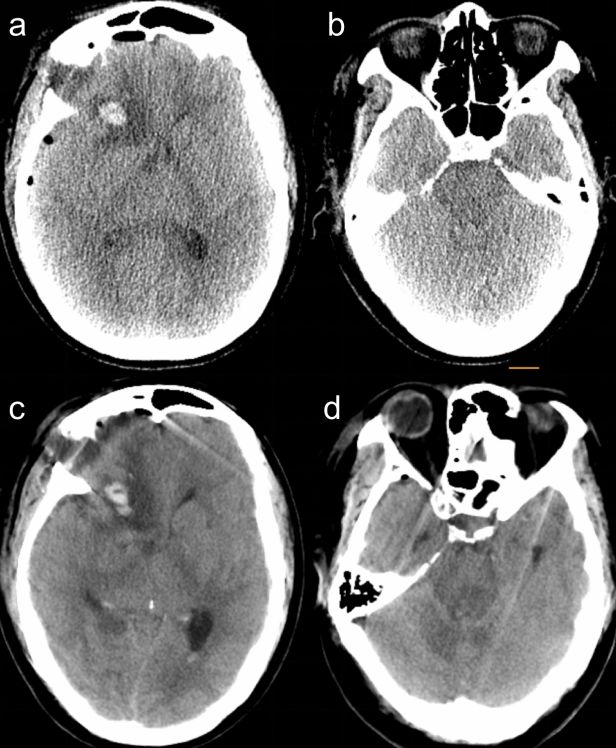

考虑可能腰大池脑脊液引流过量,予立即夹闭腰大池引流管,1h后患者意识较好转,GCS10分,右侧瞳孔直径仍为3.5mm,左侧瞳孔直径为3mm,对光反射稍迟钝。考虑术区血肿及水肿存在,中线移位,与患者家属充分沟通后予急诊行右侧开颅血肿清除术+去骨瓣减压术(术中发现颅压尚可,去除原骨瓣,未予扩大骨窗减压),同时拔除腰大池引流管。术后患者即清醒,双侧瞳孔等大等圆,直径3mm,光反射灵敏,四肢肌力5级。复查头颅CT示中线恢复居中,环池清晰(图3)。于术后2周顺利出院。

图3. 术后头颅CT:前交通动脉瘤夹闭术后改变,中线居中,环池清晰。